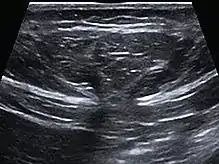

Abdominal ultrasound of a midline epigastric hernia.

Ultrasonography is also used for diagnostic purposes.